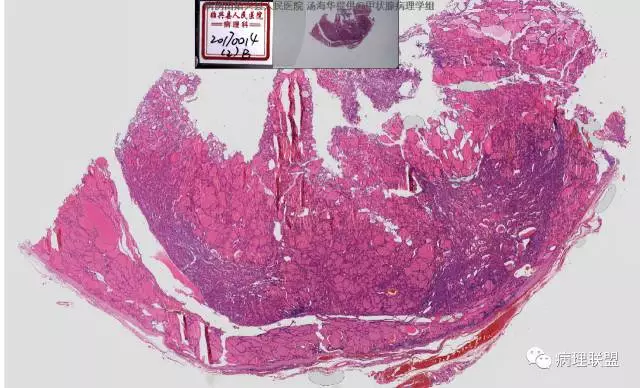

患者,女,45岁,发现双侧甲状腺肿物半月余。大体所见:左侧甲状腺肿物:4.3*5*4cm肿物一个,包膜完整,光滑,质脆,中央见出血。右侧甲状腺组织:3*1.6*1.5cm及1*1*0.8cm组织两块,其中较大的组织切开见内有0.8cm及1.2cm两个,质硬,灰白色,界不清,较小的,切开见灰黄色,质脆。